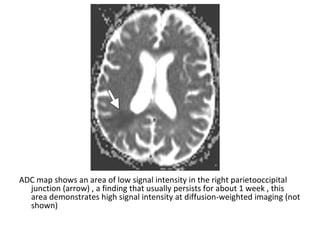

ADC map shows an area of low signal intensity in the right parietooccipital

junction (arrow) , a finding that usually persists for about 1 week , this

area demonstrates high signal intensity at diffusion-weighted imaging (not

shown)

T1 shows an area of low signal intensity (arrow)

T2 shows an area of high signal intensity (arrow)

FLAIR shows an area of high signal intensity (arrow)